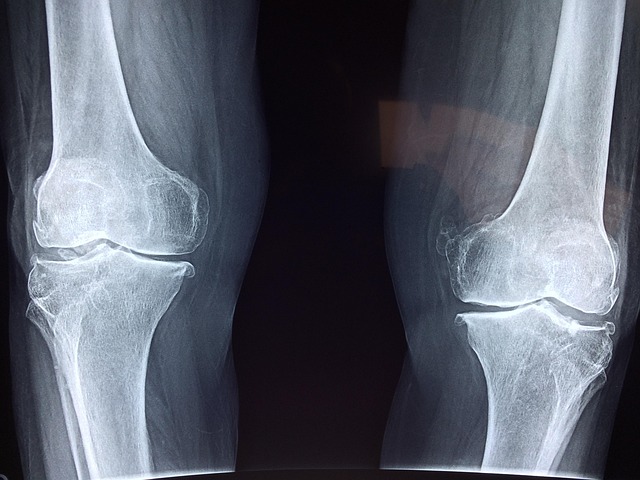

관절은 우리 몸의 움직임을 가능하게 하는 중요한 구조로, 나이가 들면서 자연스럽게 퇴행이 진행됩니다. 무릎, 고관절, 어깨, 손목 등 다양한 관절은 뼈와 근육을 연결하며 부드러운 움직임을 돕습니다. 하지만 과도한 사용, 잘못된 자세, 영양 부족, 노화 등의 요인으로 인해 관절이 약해지면 관절염, 연골 손상, 관절 통증 등의 문제가 발생할 수 있습니다.

관절 건강을 지키기 위해서는 적절한 운동과 균형 잡힌 영양 섭취가 필수적입니다. 관절을 보호하는 근육을 강화하고, 염증을 줄이는 식습관을 유지하면 오랫동안 건강한 움직임을 유지할 수 있습니다. 특히, 관절이 약해지는 것을 예방하기 위해서는 관절을 과도하게 사용하지 않도록 주의하면서도 적절한 운동을 지속해야 합니다.